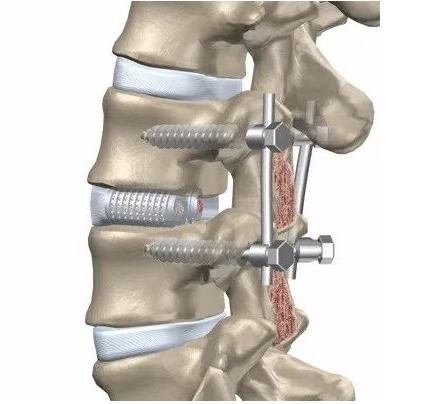

打钉子、做固定,固定和融合其实是两种不同的术式。虽然我们常常在固定的同时也做了融合,但也有部分病人我们只做固定,不做融合。比方说,有一部分胸腰椎的骨折,我们只做固定,为骨折愈合创造一个条件,将来等到骨折愈合之后,这个钉子可以去掉。

绝大多数的内固定物,就是我们说的“钉子”,目前绝大部分都是钛合金的,钛合金本身的组织相容性特别好,它对机体的影响非常小,所以就算钉子不取,对机体也没有明显影响。所以对于椎体间进行了融合的患者,大多数情况下,不建议取内固定。

对于需要取的患者,比方说胸腰椎的骨折,我们主张在一年左右的时间把内置物取掉。当然你晚一点取,也没有太大的问题。甚至有的人说我不取它,将来万一钉子在体内断了,断了再取其实也是可以的。唯一的问题,断了钉子之后再取稍微困难一点,有可能断钉的残端有可能取不出来,但取不出来对人体也几乎没有影响。